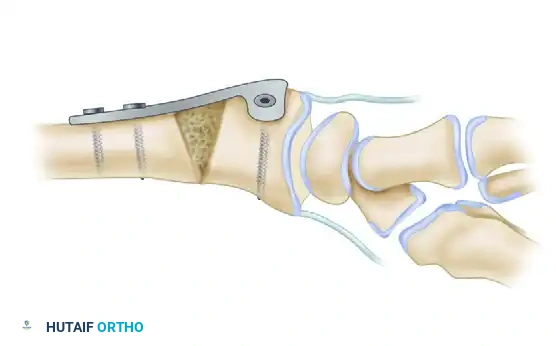

5. Bone Graft Harvesting and Insertion

Based on the defect created by the lamina spreader and the preoperative template, harvest a corticocancellous block from the contralateral iliac crest. Contour the graft meticulously.

Insert the contoured graft into the osteotomy defect. Ensure that the cortical face of the graft is positioned volarly to provide structural buttressing against compressive forces.

6. Internal Fixation

Stabilize the osteotomy and the intercalary graft using a robust volar plate. Historically, a 3.5-mm angled T-shaped plate was utilized, though modern anatomically contoured volar locking plates are now frequently employed.

💡 Clinical Pearl: Correcting Pronation Deformity

Distal radius malunions frequently feature a supination deformity of the shaft relative to a pronated distal articular fragment. When the flat surface of a rigid volar plate is applied and compressed to the volar aspect of the radius, it inherently acts to derotate the distal fragment, effectively correcting the pronation deformity.